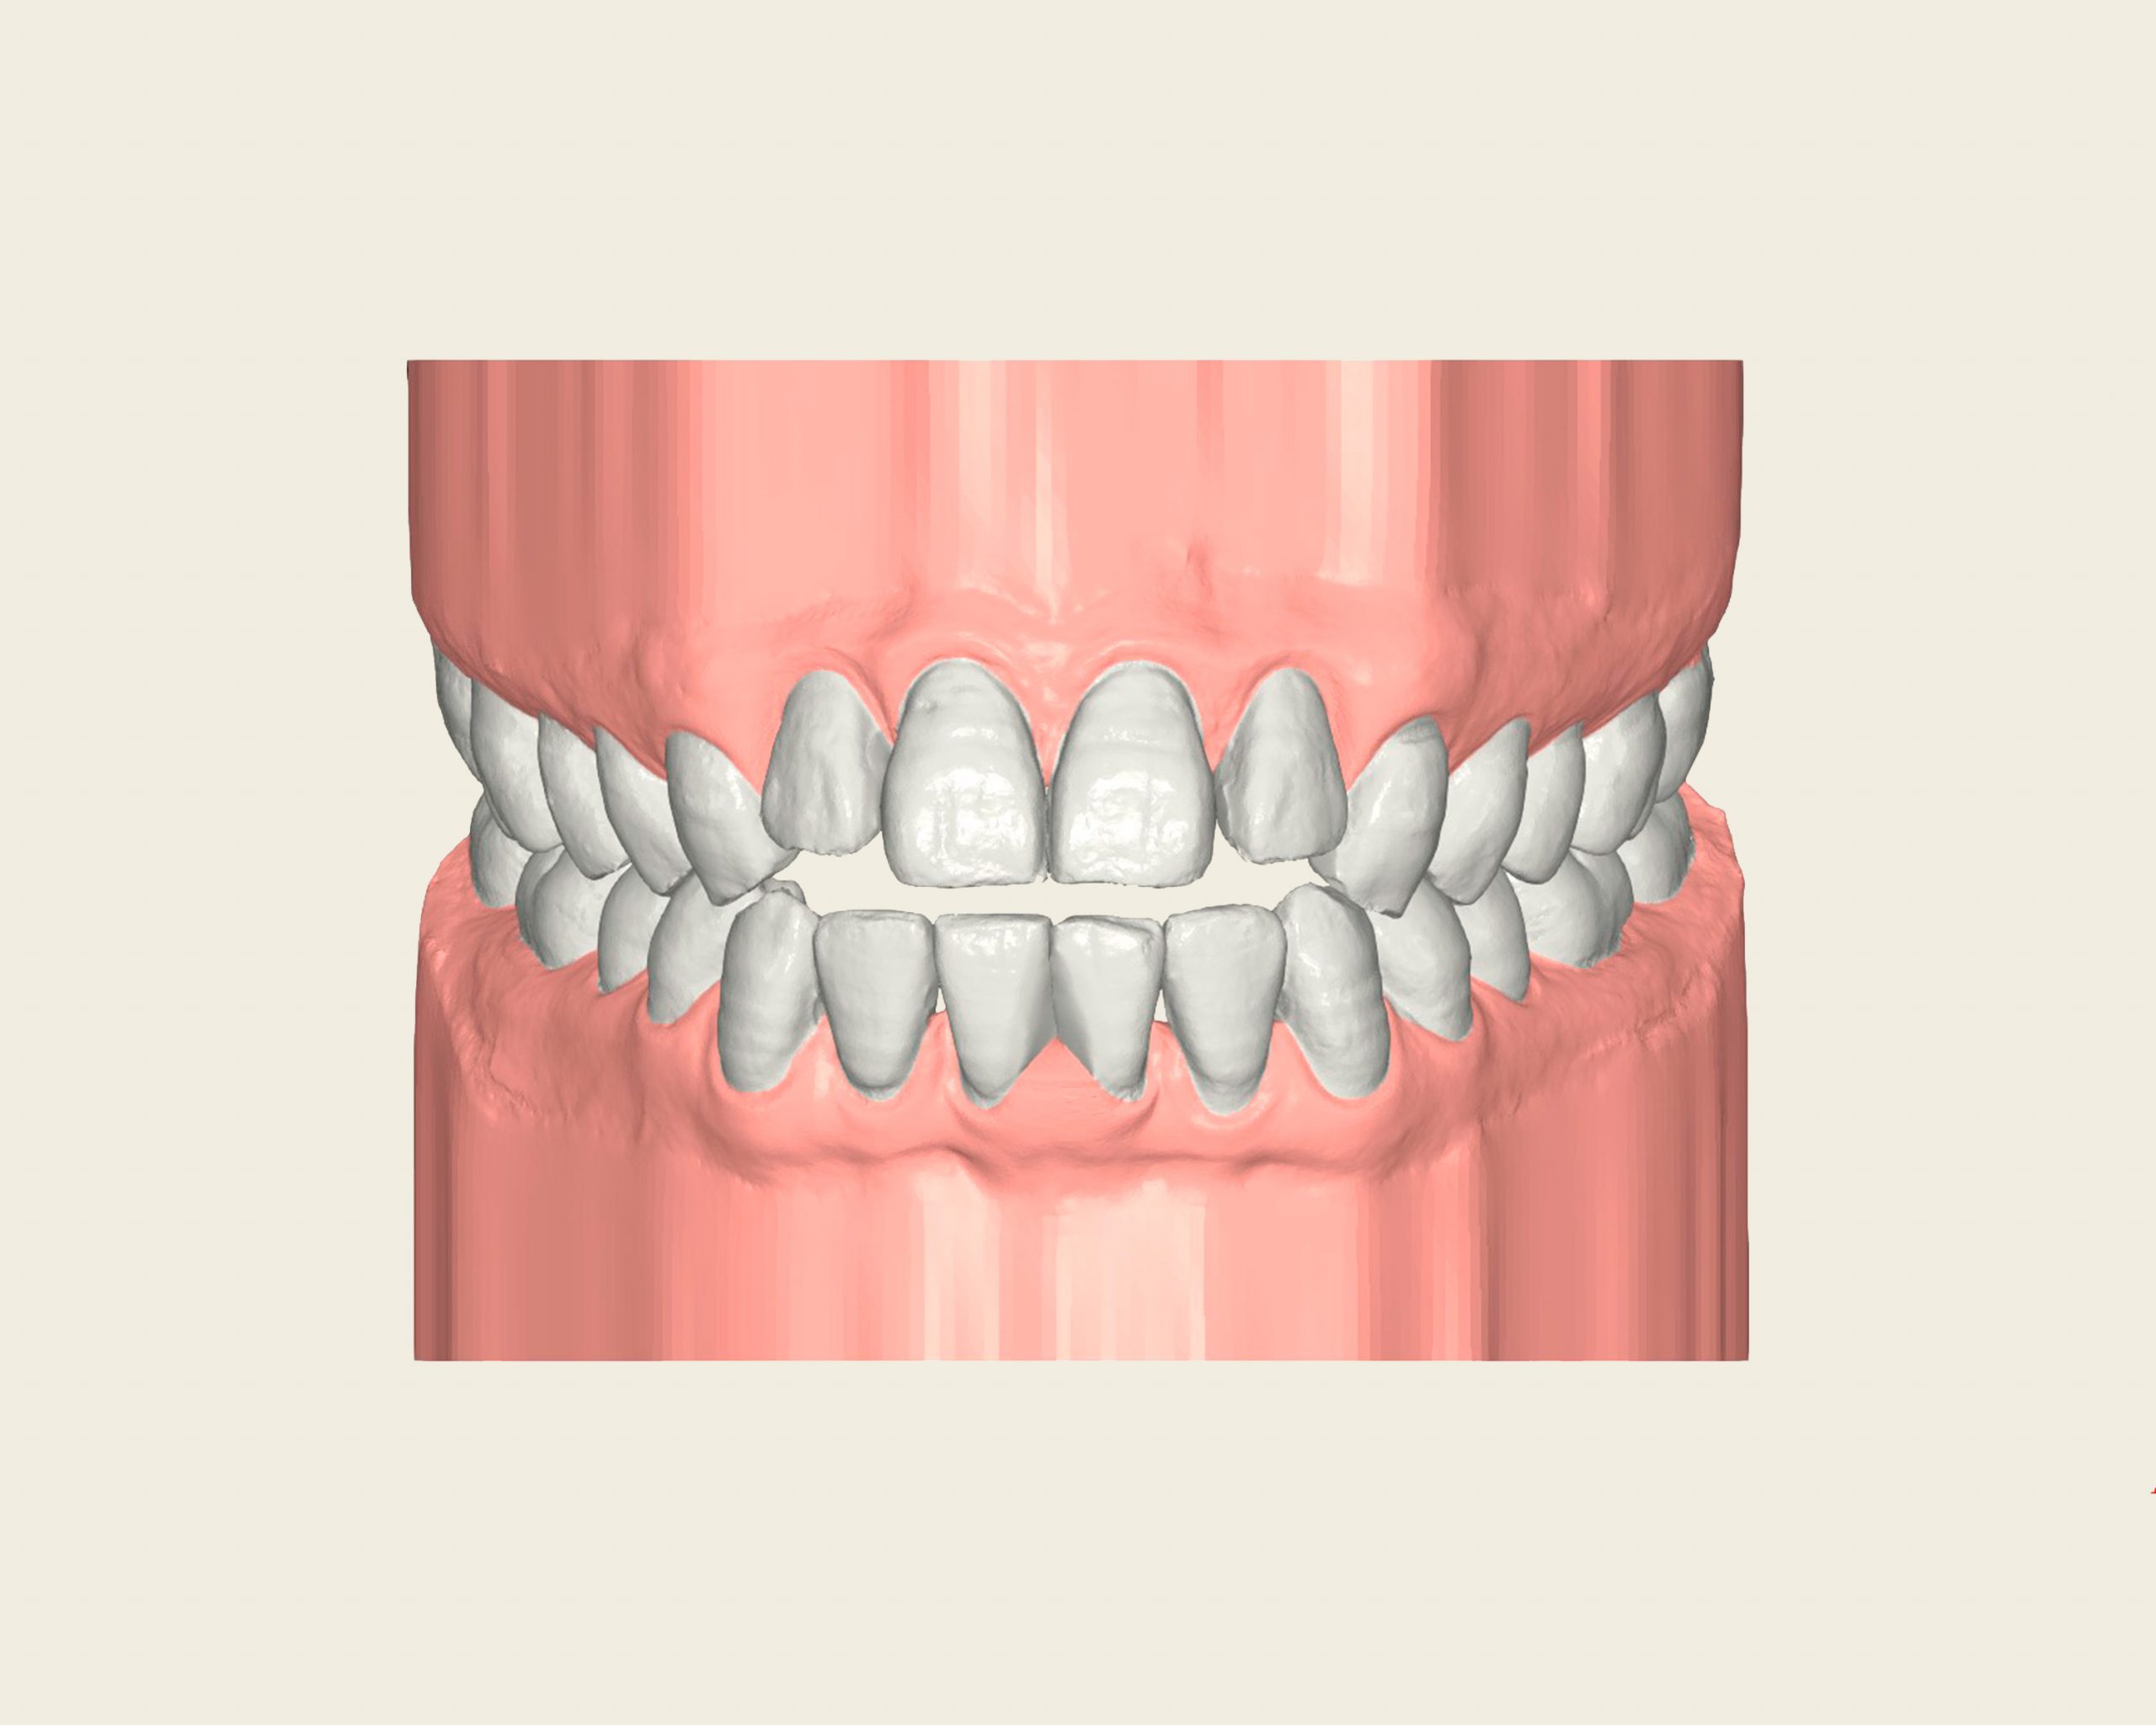

Maloclusión

Se caracteriza por una alineación incorrecta de los dientes, donde los dientes superiores e inferiores están en una relación normal, pero hay una falta de espacio que provoca que los dientes se solapen o estén apiñados.

Este problema puede generar dificultad para mantener una correcta higiene dental y afectar la estética de la sonrisa

INITIAL

22 Semanas de Tratamiento